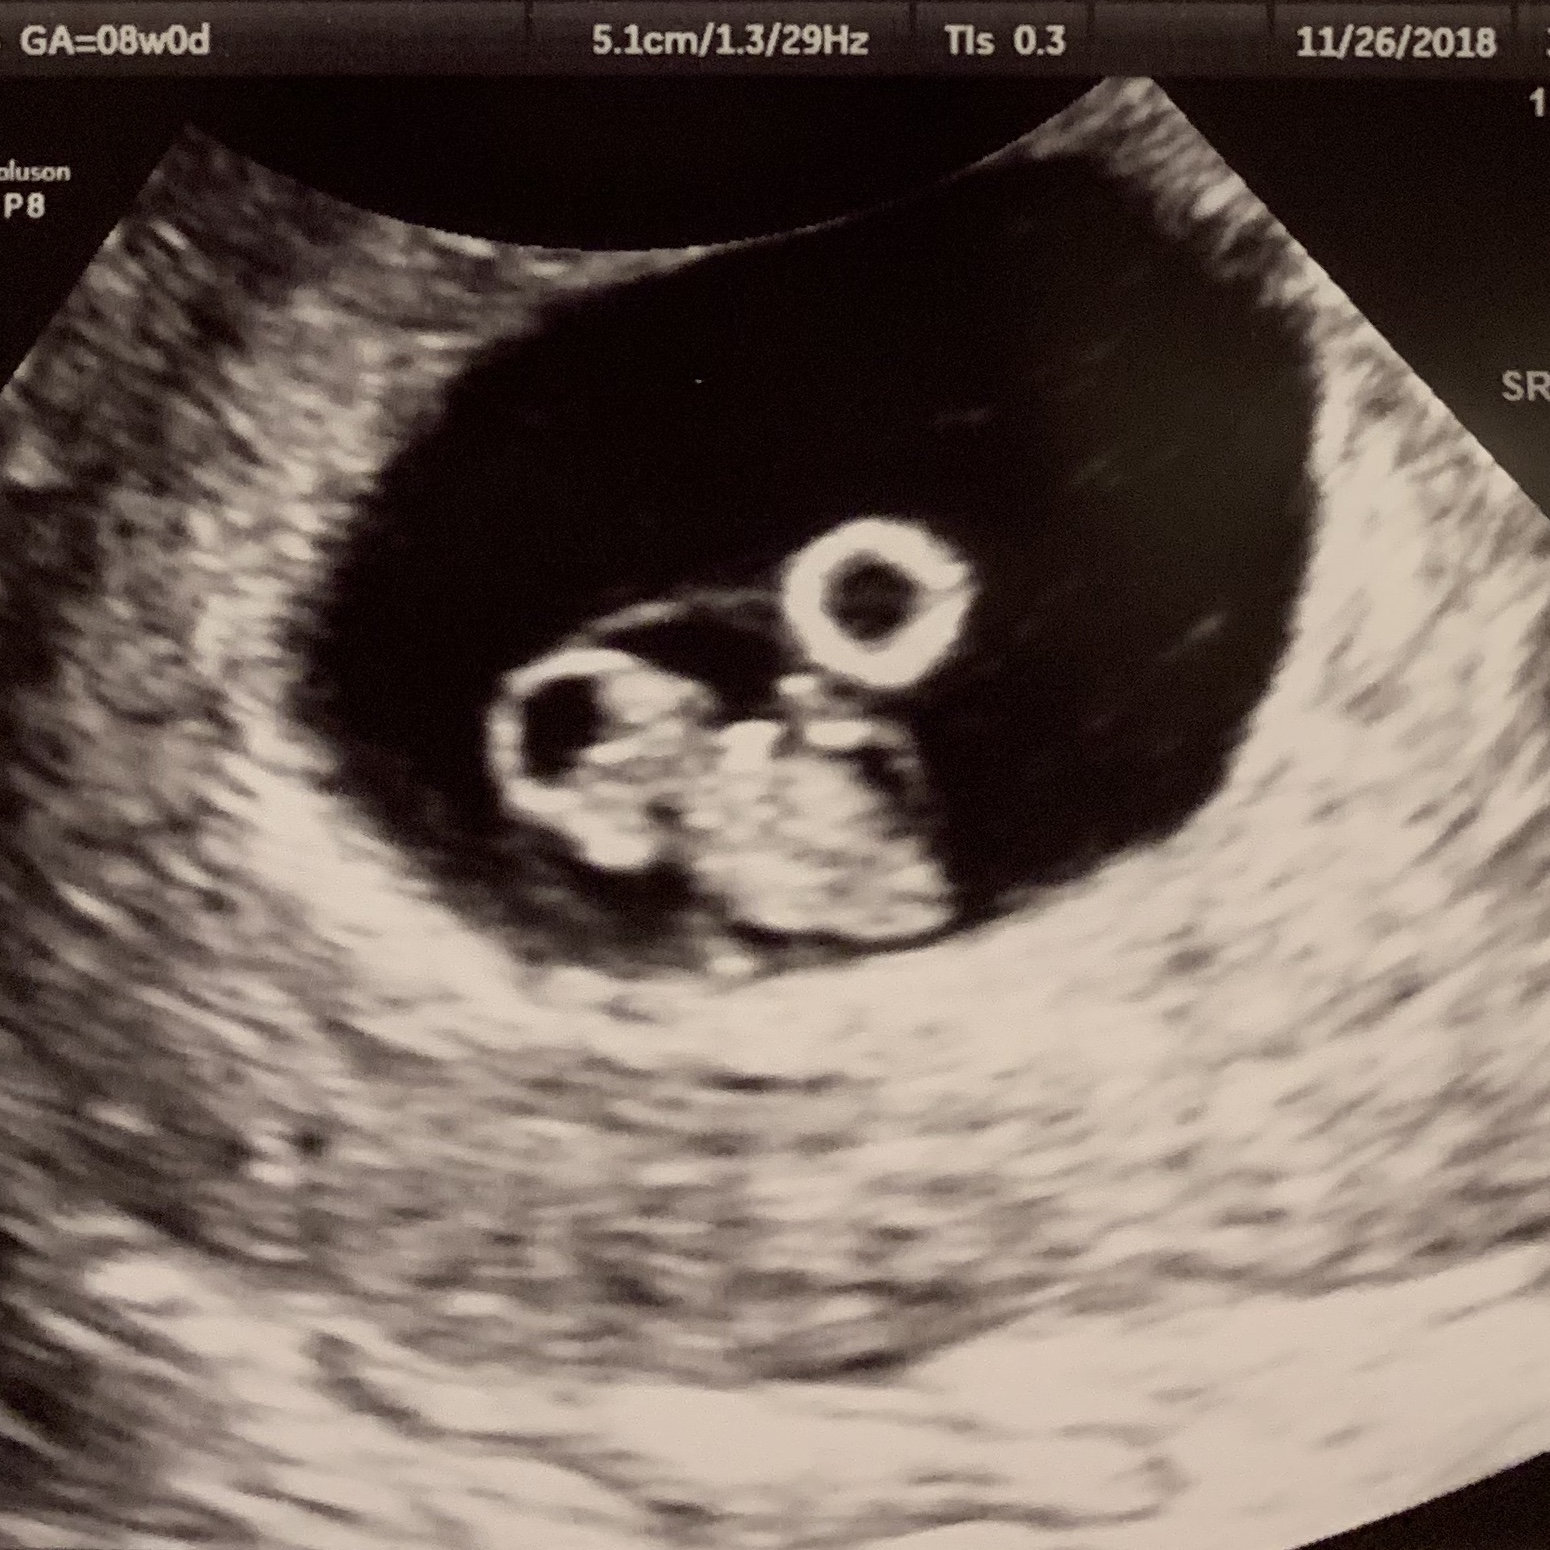

7 weeks 5 days two tiny babies and two tiny heartbeats 😍😍